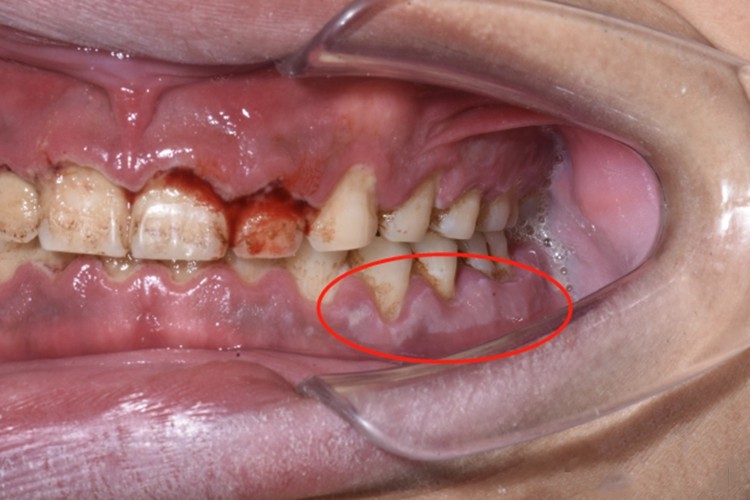

急性坏死性龈口炎早期牙龈边缘及龈乳头红肿、充血,以后迅速坏死,使龈缘变平,表面覆盖灰褐色污秽假膜,即口腔局部的白斑,患处牙龈易出血,疼痛明显,口内有特殊的坏死性口臭。

急性坏死性龈口炎患者需尽早遵医嘱给予抗感染治疗,如早期可刮去坏死组织及大块牙石,使用过氧化氢溶液冲洗;再遵医嘱使用甲硝唑片、维生素C片等药物,还可选择银花、甘草等中药煎水漱口。